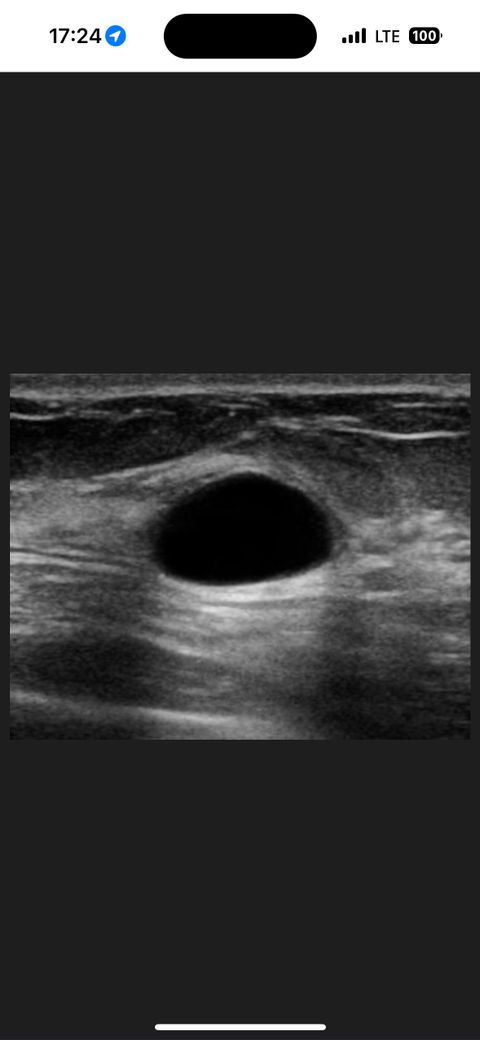

제 아내가 유방초음파 후 조직검사를 받았는데요

따로 영상이나 사진을 따로 같고있는건

없구요,

초음파를 선생님이랑 같이봐서 모양이나 크기를

정확하게 기억한다며

인터넷에서 가장 똑같은 사진을 찾아서

보여주더라구요

크기는 9mm라고 1cm정도되면 조직검사받는게좋다고해서 받았다는데

사진보시고 어떤지 고견 부탁드릴게요

업로드해주신영상의 경우는 유방낭종입니다

양성질환으로 크게 걱정하실 건 없습니다

조직검사는 필수는 아닙니다.